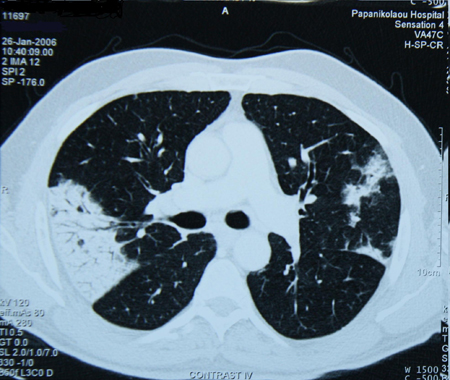

Os aerossóis inalados provenientes de cigarros eletrônicos podem conter substâncias nocivas ou potencialmente nocivas (por exemplo, metais pesados, partículas ultrafinas, compostos orgânicos voláteis e outros produtos químicos). Os achados radiológicos em pessoas com doença pulmonar grave associada ao uso de cigarro eletrônico incluem infiltrados pulmonares na radiografia torácica e infiltrados bilaterais com opacidade em vidro fosco na TC de tórax.[45]Schier JG, Meiman JG, Layden J, et al. Severe pulmonary disease associated with electronic-cigarette-product use - interim guidance. MMWR Morb Mortal Wkly Rep. 2019 Sep 13;68(36):787-90.

[Figure caption and citation for the preceding image starts]: Tomografia computadorizada (TC) do tórax de paciente com toxicidade pulmonar por amiodarona, mostrando opacidades assimétricas com distribuição periféricaDo acervo de Athanasia Pataka, MD [Citation ends].